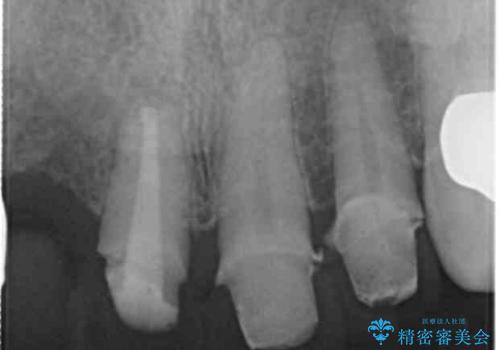

- 前歯の痛み・排膿・ぐらつきの改善を求めて来院されました。

視診・X線写真検査より根尖性歯周炎が認められ再治療が必要な状態です。

再根管治療を行うべくクラウン除去を行ったところ、右上側切歯に保存不可能な垂直性の破折が認められたため抜去が必要になりました。

即切歯の抜歯を行う場合犬歯を含めたブリッジによる補綴計画を立てることが多いですが、今回は犬歯から大臼歯にかかる大きなブリッジが既に装着されていたため予算とご希望を相談し前歯のみの延長ブリッジ補綴で治療を行っていくこととしました。